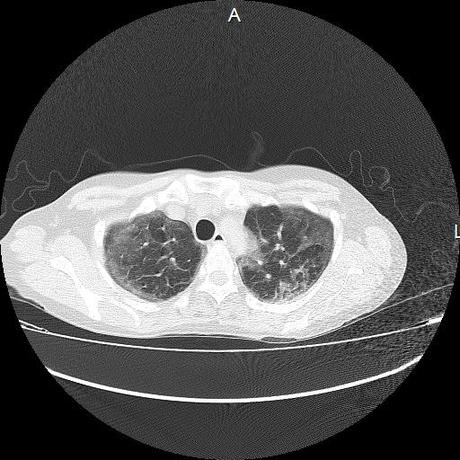

El parénquima pulmonar con areas parcheadas difusas en vidrio despulido combinadas con otras areas hipodensas de baja atenuación debidas a atrapamiento aéreo y engrosamiento intersticial y zonas de fibrosis de predominio en lóbulos medios e inferiores de ambos pulmones.

- LOS HALLAZGOS PUEDEN ESTAR EN RELACIÓN A NEUMOPATIA INTERSTICIAL PROBABLE ETIOLOGIA HIPERSENSITIVA VS AUTOINMUNE/BACTERIANA/FUNGICA.